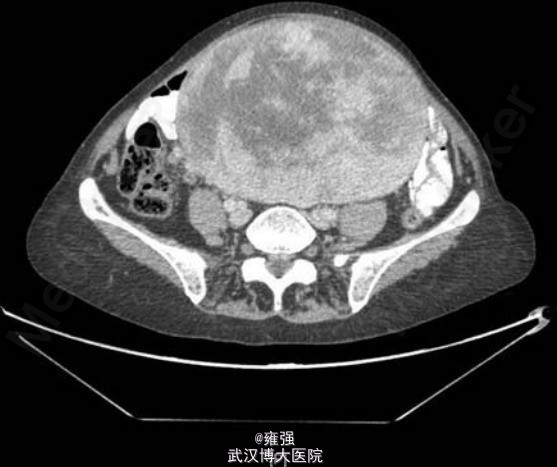

辅检:肿瘤标记物(CEA、CA19-9、CA125)均在正常范围,入院后腹部X片示下腹部出现增强的不透光区(如下图示)。术前TAP分段CT示盆腔内大型、界限清楚、中线测量为 18.8 cm×13.3 cm×18.2 cm、混合衰减的包块(如下图示),位于子宫前、膀胱之上,独立于子宫存在,考虑为起源于卵巢。

诊断:术前诊断“卵巢癌”,拟行子宫全切+双侧输卵管+卵巢切除+网膜切除术。 术中发现卵巢和子宫正常,但见小肠系膜前表面有一个大型包囊的包块(如下图示),肿物距离十二指肠空肠曲 340 cm 远,回肠末端 30 cm 远,因此完整切除回肠末端、小肠系膜和小肠,一期吻合。 术后病理示: 41 cm长小肠,大小为 18 cm×15 cm×11.5 cm 的卵状团块伴有完整和部分的纤维化包囊,为肾上腺外副交感神经节瘤。此瘤具有纤维包囊、由统一细胞组成的可变固性的小叶和巢状成分(如下图示)。肿瘤免疫组化显示嗜铬素A、突触素、CD56、S100 和 5%Ki67 阳性,在一个切片中发现存在淋巴血管微浸润。